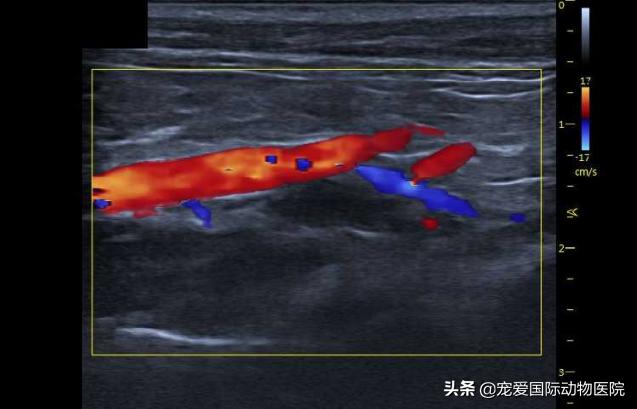

彩超检查:提示

肥厚性心肌病与腹主动脉血栓

在腹主动脉超声中可见

腹主动脉终端血流信号消失

超声:可见血栓消失